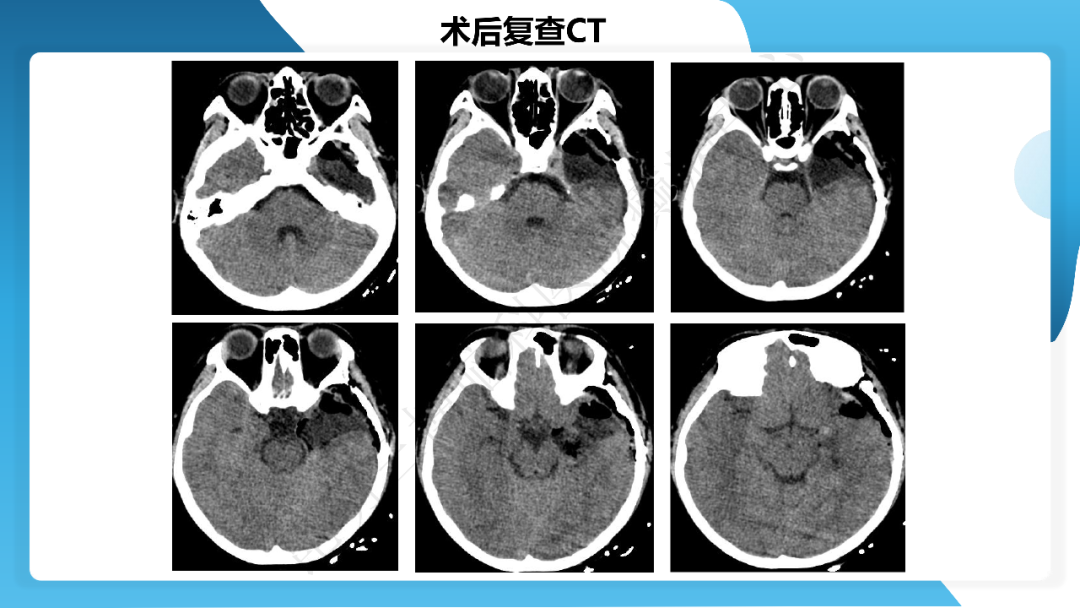

《「痫停」信步》癫痫治疗病例荟萃第四十三期---左侧颞前叶及内侧结构切除手术治疗局灶性癫痫一列